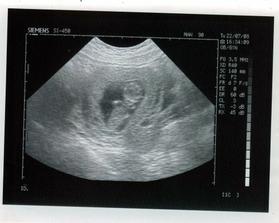

Na prehliadky som zo začiatku chodila každé 2 týždne, neskôr každý mesiac. Drobčeka som videla poriadne prvý krát videla v 12. týždni, hýbal rukami, nohami, kotrmelce robil... Bolo to strašne zlaté, vedela by som sa na to pozerať hodiny. 🙂 Na ďalšiu prehliadku idem v 17. týždni, zoberiem si mobil a natočím si to. 🙂